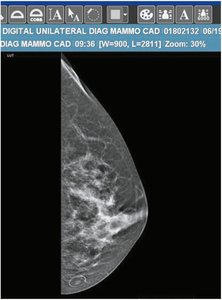

Procedure suffixes: -ectomy, -gram, -graphy, -metry, -scope, -scopy, -tomy (e.g., appendectomy, mammogram)

Example: A mammogram is an x-ray image of the breast. The suffix -gram means picture or record.